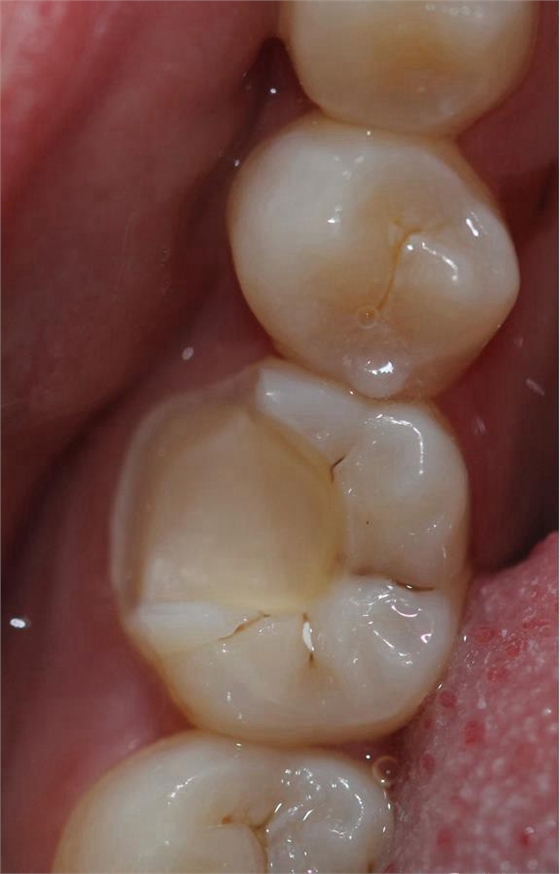

根管治療完之后,樹脂墊底,不需要加樁 不管你是做樹脂嵌體還是瓷嵌體。

牙體根充完制備 ,剩余的牙體組織最小的厚度為2mm。

畫線是最關(guān)鍵的,線畫不好制出的修復(fù)體會出現(xiàn)邊緣缺損 或多 或少,醫(yī)生和技術(shù)配合

掃描 畫線 準(zhǔn)備研磨